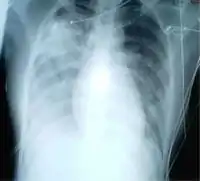

У загальному аналізі крові спостерігають нормоцитоз або лейкопенію на тлі вираженої лімфопенії та тромбоцитопенії. Зміни в легенях варіюють від інтактної рентгенологічної картини до розповсюдженої двобічної багатофокусної інфільтрації легеневої тканини. Приблизно в половині випадків виникають однобічні монофокусні затемнення, в інших випадках — двобічні багатофокусні затемнення. Характерним є відсутність плеврального випоту, деструктивних змін в легенях та внутрилегеневої лімфаденопатії. У біохімічному аналізі крові нерідко виявляють підвищення активності креатинфосфокінази, амінотрансфераз — АлАТ і АсАТ.